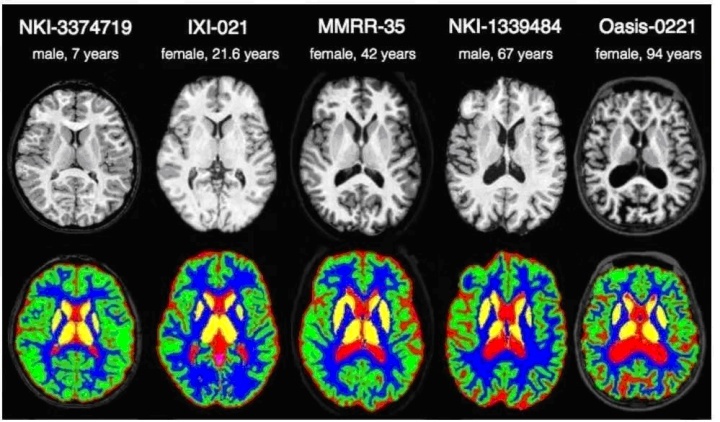

举例而言,在下图中展示了一种肺部CT切片的可视化结果。该图像经过预处理后已被转换为灰度图像状态,并呈现明显的组织与器官界限。而图二则展示了不同个体的脑MRI图像数据,则显示出显著差异性特征。这对脑组织的具体提取工作而言确实存在诸多挑战性问题。

图二 不同个体的脑MRI成像结果